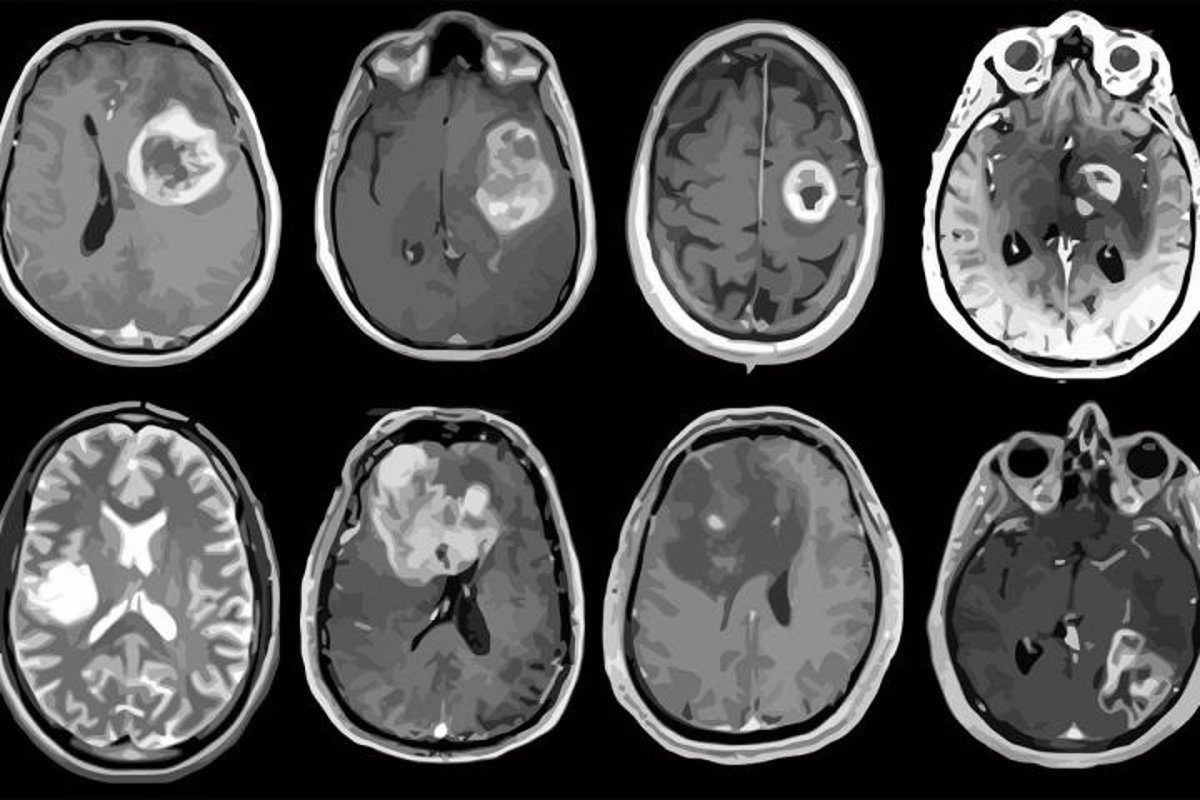

BREAKING: The FDA has approved Modeyso™ (dordaviprone), the first drug for diffuse midline glioma (DIPG) with the H3 K27M mutation. DMG/DIPG is a rare and aggressive brain tumor that mostly affects children and young adults. This is a long-awaited step forward for a devastating

BREAKING: The FDA has approved Modeyso™ (dordaviprone), the first drug for diffuse midline glioma (DIPG) with the H3 K27M mutation. DMG/DIPG is a rare and aggressive brain tumor that mostly affects children and young adults.

El tratamiento experimental se centra en el glioblastoma, el tumor cerebral primario maligno más común en adultos y altamente resistente a la quimioterapia y radioterapia. #Cancer #Salud #CONICET #Ciencia #Tecnología Lab Candolfi, FMed.⭐⭐⭐ periferia.com.ar/investigacion/…

El tratamiento experimental se centra en el glioblastoma, el tumor cerebral primario maligno más común en adultos y altamente resistente a la quimioterapia y radioterapia.